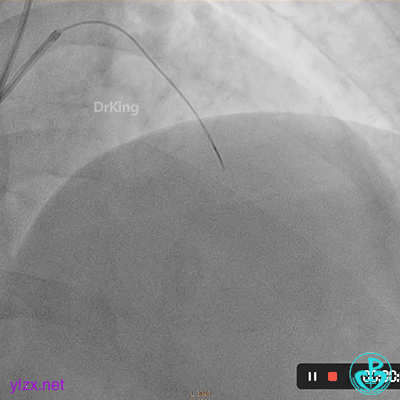

07 2个月后再次造影

处理前降支病变,导丝Pilot 50通过LAD病变到达远段,沿导丝送入穿通导管至远段,回抽有血,造影提示在真腔。

PTCA球囊扩张后无前向血流,以硝普钠反复行冠脉内局部药物释放治疗术。

复查造影提示LAD血流恢复TIMI血流2-级。